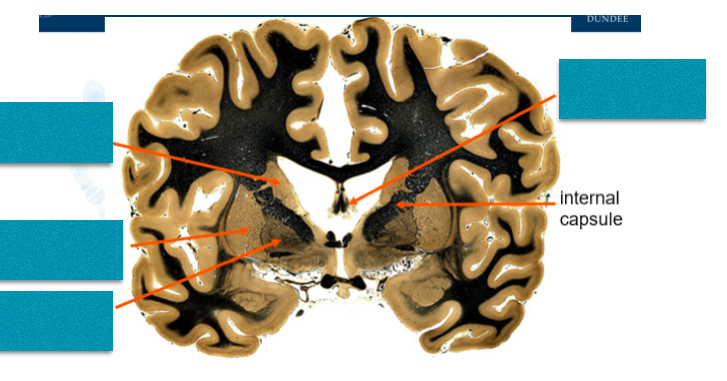

Fill in the blanks.